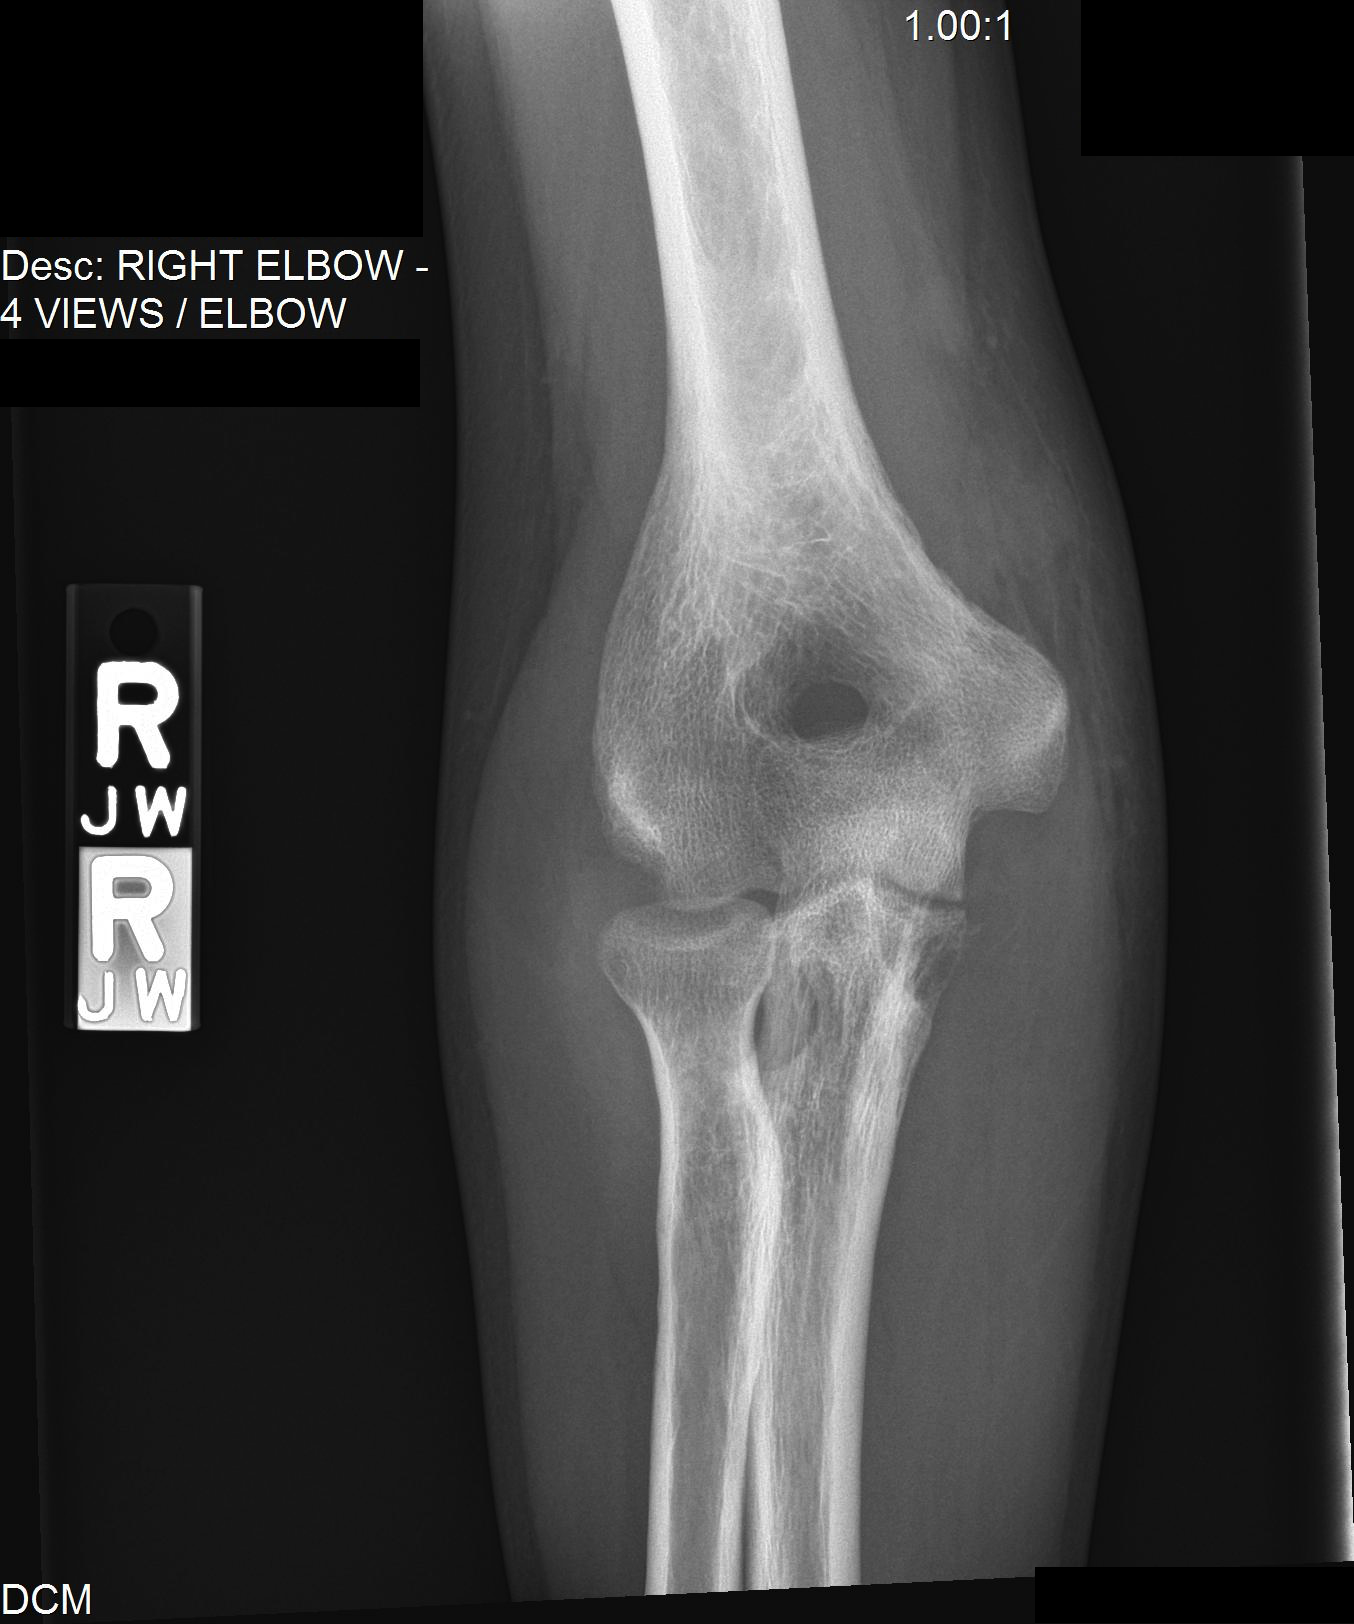

Tuberculous Arthritis Elbow Radiology . Tuberculous arthritis of the right elbow. Frontal (a) and lateral (b) plain radiographs demonstrate multiple osteolytic lesions within the ulna,. To assess magnetic resonance (mr) imaging features in differentiating tuberculous arthritis from pyogenic arthritis. Tuberculous arthropathy is a type of musculoskeletal manifestation of tuberculosis (tb) and a common cause of infectious arthritis in. Periarticular osteopenia, cortical erosion, narrowing of the joint space, minimal periosteal reaction, and calcification of. Fourteen patients with tubercular arthritis of elbow were evaluated. Mri is a highly sensitive technique which demonstrates fine anatomical details and identifies the early changes of arthritis, which are not visible on radiographs.

Tuberculous arthritis of the right elbow. Frontal (a) and lateral (b) plain radiographs demonstrate multiple osteolytic lesions within the ulna,. Periarticular osteopenia, cortical erosion, narrowing of the joint space, minimal periosteal reaction, and calcification of. Tuberculous arthropathy is a type of musculoskeletal manifestation of tuberculosis (tb) and a common cause of infectious arthritis in. Mri is a highly sensitive technique which demonstrates fine anatomical details and identifies the early changes of arthritis, which are not visible on radiographs. Fourteen patients with tubercular arthritis of elbow were evaluated. To assess magnetic resonance (mr) imaging features in differentiating tuberculous arthritis from pyogenic arthritis.

tuberculosis elbow case. Anteroposterior radiograph of the right Tuberculous Arthritis Elbow Radiology Frontal (a) and lateral (b) plain radiographs demonstrate multiple osteolytic lesions within the ulna,. To assess magnetic resonance (mr) imaging features in differentiating tuberculous arthritis from pyogenic arthritis. Fourteen patients with tubercular arthritis of elbow were evaluated. Tuberculous arthritis of the right elbow. Periarticular osteopenia, cortical erosion, narrowing of the joint space, minimal periosteal reaction, and calcification of. Tuberculous arthropathy. Tuberculous Arthritis Elbow Radiology.